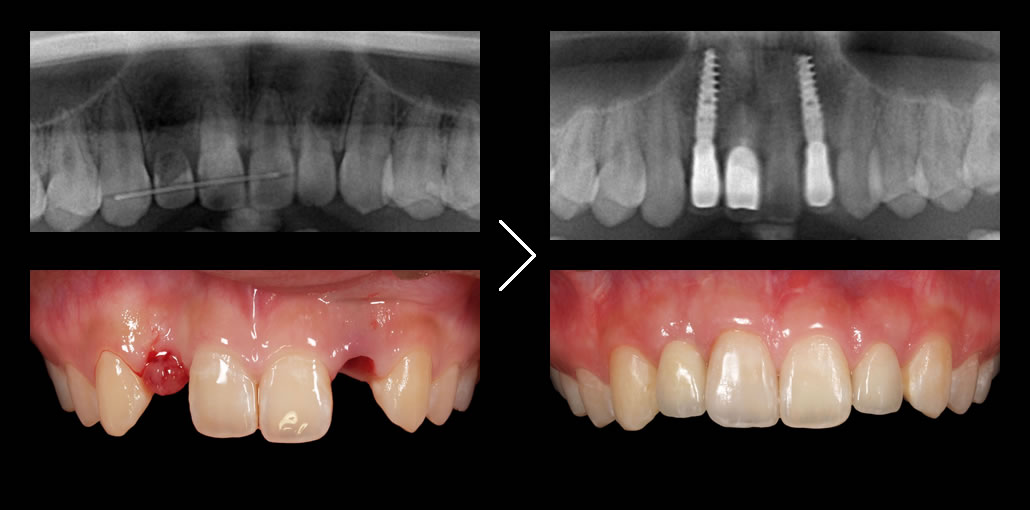

当院が最も得意とするのが前歯のインプラントです。

奥歯(臼歯部)で、十分な骨がある場合のインプラントは極めて簡単です。一方、インプラントを固定する骨が十分にない前歯のインプラントが最も難易度が高くなります。前歯は目立つため、見た目の美しさを気にして患者様の要求水準が高まるのも前歯のインプラントの特徴です。 こういった症例では、技術的に難しいため、インプラント治療ではなくブリッジでの治療を勧める歯科医院が多いのが現実です。

私たちが最も得意とするのがこの前歯のインプラント治療(審美インプラント)です。誰が見てもインプラントと分からない水準で仕上げることが可能です。

そのため、 骨が残っているところに無計画にインプラントを埋入するケースがほとんどで、その結果インプラントの上部構造の形態に無理が生じたり、見た目の酷い治療結果となりがちです。

他医院では行わない精密な治療計画

オールオン4クリニックでは、必要に応じてインプラント治療前に歯肉や骨の調整を行い、綿密な診査・診断・3Dプランニング・ガイデッドサージェリーを駆使して、寸分のズレのないインプラント埋入を行います。